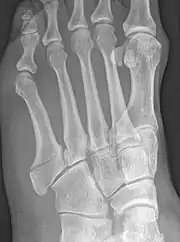

Jones fracture of the 5th metatarsal of the foot, between the epiphysis (base) and the diaphysis (shaft).

Robert Jones described the fracture of the fifth metatarsal which bears his name in the Annals of Surgery in 1902. In his paper, Jones described the fracture in a series of six patients, the first of which was himself.[8] He had injured his foot while dancing several months earlier, and had thought the injury to be to a tendon in the foot. He examined himself the day after the injury, and found that the tendon was intact, but he could not find definite evidence of bony injury. He asked a colleague, David Morgan, to X-ray his foot, and a fracture above the base of the fifth metatarsal was found. The finding of similar fractures in several patients after his own prompted him to write about it. He also noted that the fracture was not caused by direct trauma to the bone, as had always been assumed before, but by a cross-strain being applied to the bone.[9]